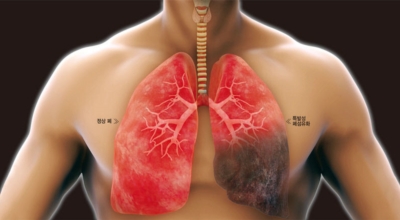

건강한 폐를 위해서는 폐의 활동을 유지하는데 도움을 주는 건강에 좋은 음식을 섭취해야 합니다. 폐는 우리 몸에서 중요한 역할을 하는 것은 말할 필요도 없어요. 그러나 결국 폐는 공기 뿐만 아니라 대기 오염과 담배 연기 같은 유해한 요소를 흡입하게 되는데요. 이런 오염 물질은 천식, 기관지염, 낭포성 섬유증 또는 폐렴등의 호흡기 건강 문제의 위험을 증가시켜요.

5. 장기간의 흡연은 기도의 보호 메커니즘을 손상시켜 기관, 기관지, 폐 간질 또는 폐에 손상을 주어 폐 기능의 건강에 영향을 미쳐요.